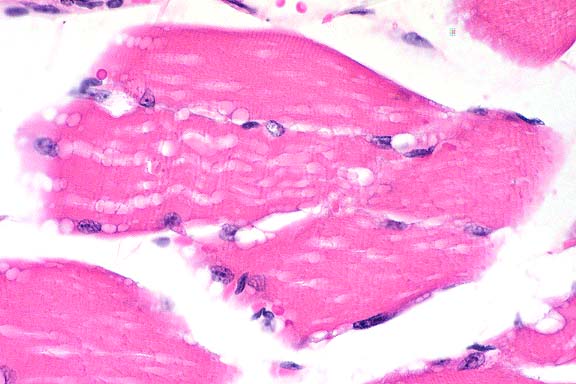

- 1. Heart and skeletal muscle: Degeneration, vacuolar, severe.

- 2. Heart and skeletal muscle: Regeneration, moderate.

Etiology: Abnormal storage of glycogen in cardiac myocytes

and skeletal muscle. Condition: Glycogen Storage Disease Type

II.

- The periodic acid-Schiff (PAS) reaction shows that many vacuoles

are PAS positive and diastase sensitive (longer diastase digestion

times may have to be used). No evidence of heart failure has

been seen as yet. Mice will be used as models for gene therapy.

40x

obj

- Case 15-1. Heart. Moderate numbers of cardiac myocytes

contain large vacuoles.

- Case 15-1. Skeletal muscle. Muscle fibers have cytoplasmic

vacuolation.